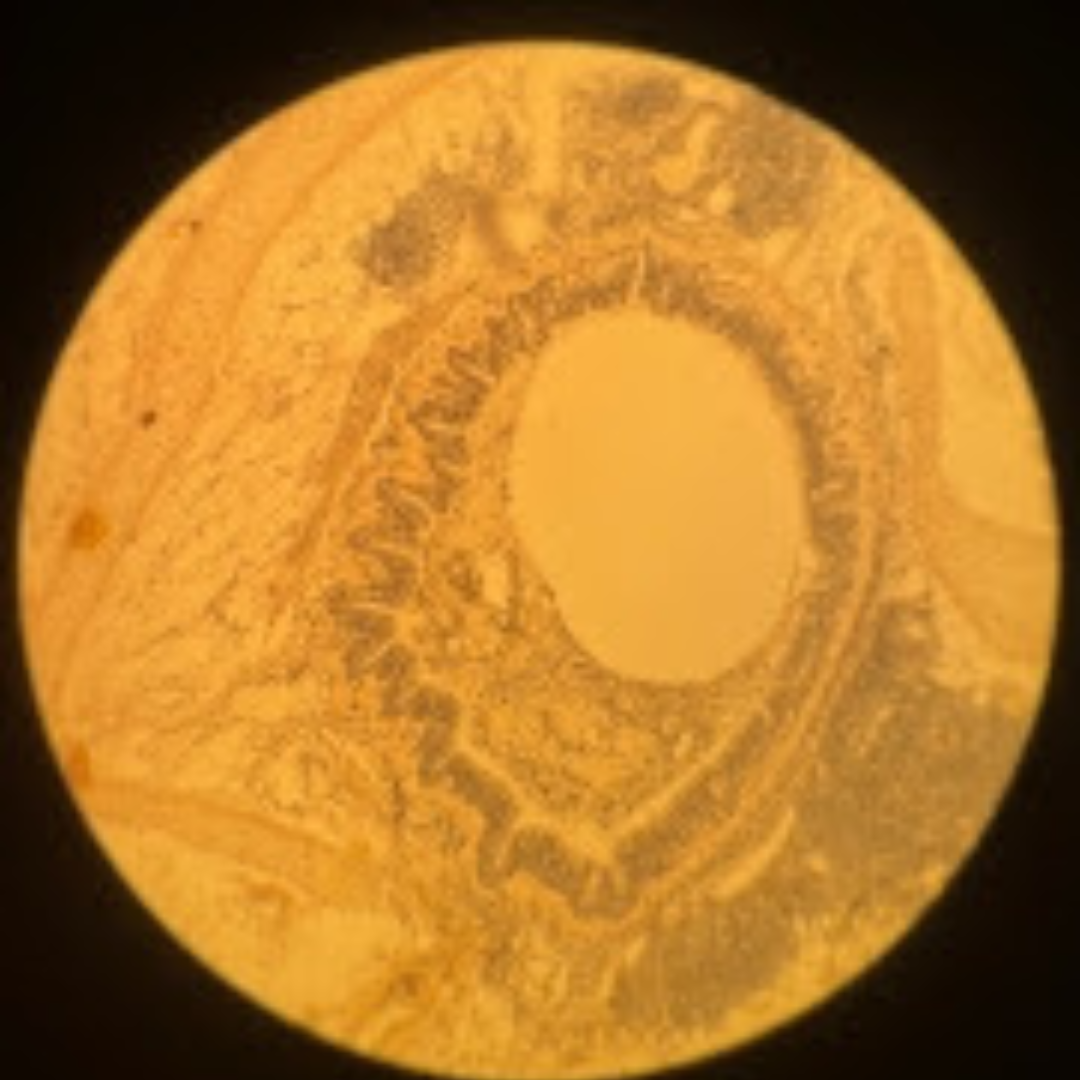

Jejunum

Duodenum

Jejunum

Jejunum

Jejunum

Jejunum

Jejunum

Jejunum